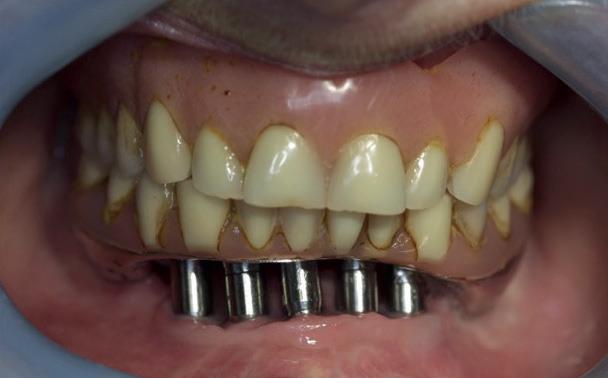

9). In de bovenkaak werd bilateraal een sinuslift uitgevoerd. Aansluitend werden in beide kaakhelften implantaten geplaatst (afbeelding 10).

13. Techniekmodel

plaatsing van de restauraties werden zowel de tandboog als de tandstand in de bovenkaak gecorrigeerd (afbeelding 13-15).

Aansluitend werd de onderkaak volgens hetzelfde principe gerehabiliteerd, resulterend in een stabiele, functionele en esthetisch gebalanceerde occlusie (afbeelding 16-17).